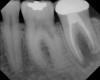

Figure 7  Clinical case of internal root resorption that was treated by orthograde root canal therapy.

Figure 7

Figure 8  Clinical case of internal root resorption that was treated by orthograde root canal therapy.

Figure 8